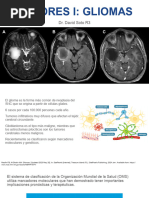

Los glioblastomas son tumores astrocíticos malignos (grado IV de la clasificación

de la OMS). Representan los tumores más frecuentes en el adulto. Pueden ocurrir

a cualquier edad, pero el 70% de los casos son vistos en pacientes entre 45 y los

70 años. Los tumores habitualmente se localizan en los hemisferios cerebrales,

pero pueden encontrarse en cualquier parte del sistema nervioso central.